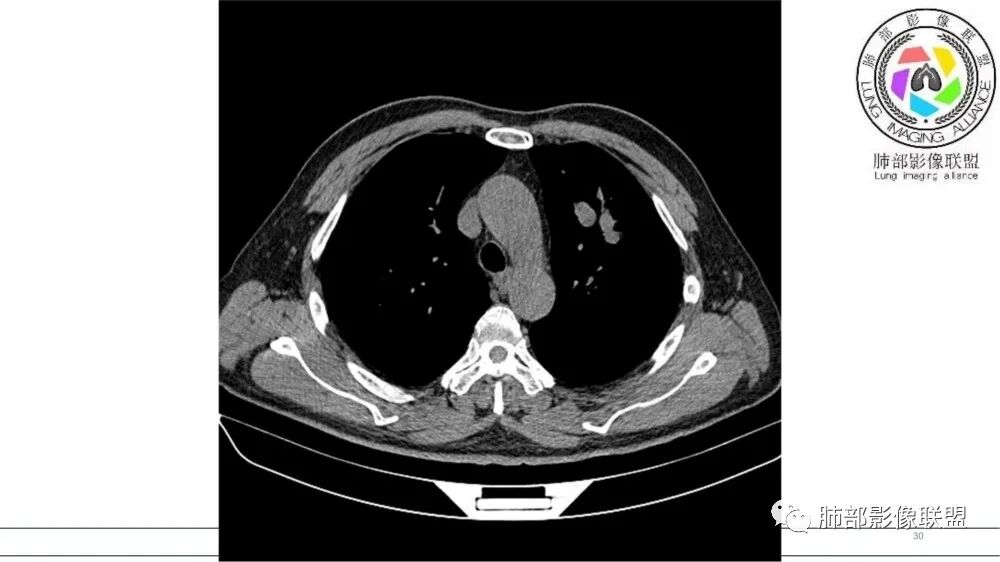

左肺上叶前段支气管内铸形生长软组织影,增强后均匀强化,远侧见斑片状磨玻璃影。考虑恶性病变,粘表?粘液腺?

老年男性,左肺上叶前段支气管内铸形阴影,增强后病灶不均匀强化,内部有坏死?远端可见斑片状阴影(阻塞性肺炎)。考虑恶性病变,老年人,鳞?类癌?粘表不能排除。

男,70岁,吸烟史,咳嗽,胸闷憋气一个月,左肺上叶不规则形软组织密度影,病灶沿支气管走形,周围见粟粒及棉絮样稍高密度影,增强扫描病灶内见少许坏死,考虑鳞癌可能,鉴别结核。

老年男性,肺气肿,吸烟史,左肺上支气管腔内铸型高密度影,呈指套状,远端多发树芽,增强不均匀强化,考虑鳞癌,鉴别小细胞癌

B3指套征,常规不是鳞癌就是ABPA,有强化丶血管造影征,倾向于鳞癌

左肺上叶支气管铸形生长,远端阻塞性炎症,增强后病灶有强化,坏死区明显。考虑中央型肺癌,鳞癌?小细胞癌?

指套征,扩张支气管内软组织强化,远侧肺野阻塞性炎,纵隔、左肺门肿大淋巴结;老年男性,吸烟,考虑鳞癌,鉴别小

指套征:是影像征象,胸部平片表现为手指状密度增高影,以肺门为中心呈放射状分布,CT显示扩张支气管内低密度黏液栓形成或实性病变,呈管状、树枝状或卵圆形密度增高影;支气管扩张伴近端梗阻时,扩张支气管内部黏液分泌物不能排出而形成。可以伴随远端空气潴留征、阻塞性炎症。

研究报道,中心型 SCLC 经 CT 扫描后通常支气管表现为鼠尾样狭窄,肺门或纵隔肿块明显,由于肿块沿管壁生长表现为顺延支气管形态的不规则形状。病灶相对特征性影像学表现比如鸭蹼状、腊肠状、葫芦状及葡萄状改变,可以出现血管包埋,很少有空洞、空泡,较少引发肺不张,阻塞性炎症成都较轻。与一般肺癌比较,恶性程度高,侵袭力强、病灶很小就容易远处转移!Herzberg 等[19]研究指出,20%以上 SCLC 倍增时间短,预后不良。